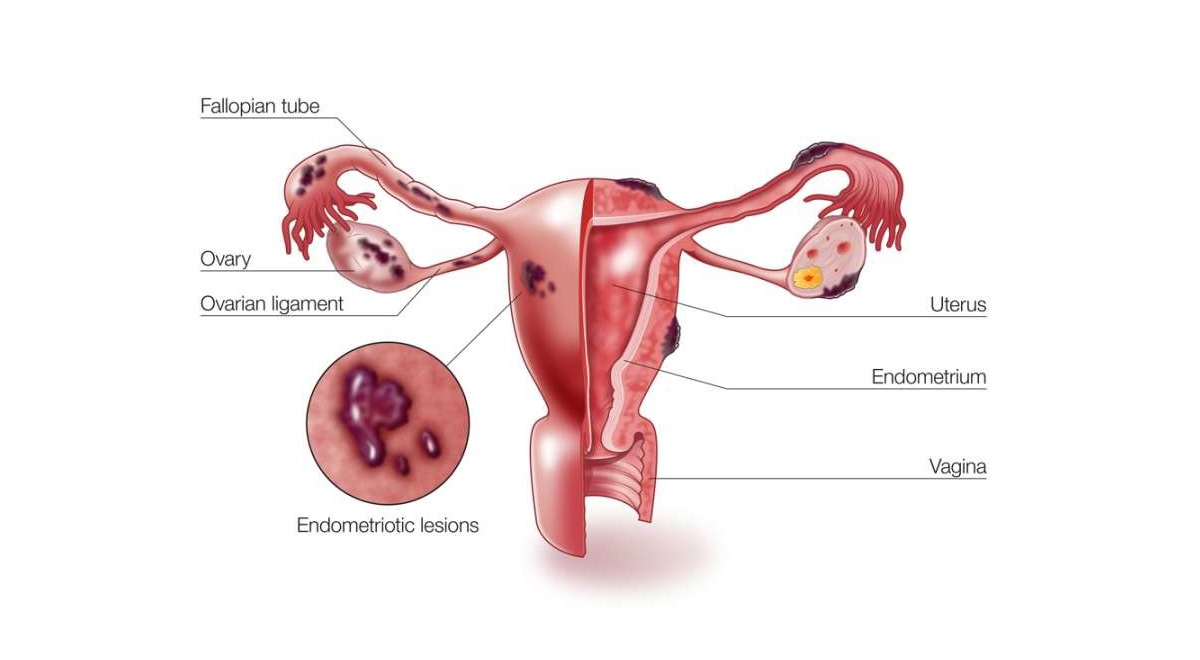

اندومتریوز؛ آندومتر بافتی است که داخل رحم را می پوشاند. اندومتریوز وضعیتی است که در آن بافتی مشابه به بافت آندومتر در خارج از قسمت رحم یافت می شود. در ناحیه لگن و شکم تحتانی (شکم) و به ندرت در سایر نواحی بدن «به دام افتاده» است. در حال حاضر مشخص نیست که چه چیزی باعث آندومتریوز می شود. عوامل متعددی وجود دارد که احتمالاً دلایل ژنتیکی، ایمونولوژیکی و هورمونی را شامل می شود.

این بیماری زمانی اتفاق میافتد که بافت مشابه با بافت داخلی رحم (آندومتر) در جایی خارج از رحم رشد میکند، معمولاً در تخمدانها، لولههای فالوپ یا سایر اندامهای لگنی. علائم آندومتریوز میتواند شامل دردهای شدید قاعدگی، درد در حین رابطه جنسی، مشکلات باروری و خونریزی غیر طبیعی باشد. با این حال، بسیاری از زنان مبتلا به آندومتریوز ممکن است بدون علائم جدی یا فقط علائم خفیف داشته باشند، که این ممکن است تشخیص بیماری را دشوار کند.

به ندرت، لکه های اندومتریوز در سایر نقاط بدن رخ می دهد. این می تواند باعث ایجاد دردهای غیرعادی در قسمت هایی از بدن شود که همزمان با دردهای پریود رخ می دهد.اندومتریوز باعث می شوددر طول سالیان متمادی تئوری های مختلفی برای علت آندومتریوز وجود داشته است. پوشش داخلی رحم (رحم) آندومتر نامیده می شود. یک نظریه این بود که برخی از سلول های آندومتر به خارج از رحم وارد ناحیه لگن می شوند. وقتی پریود میشوید، با ریختن به سمت عقب در امتداد لولههای فالوپ به آنجا میرسند.لکه های اندومتریوز تمایل دارند "چسبنده" باشند و ممکن است اندام ها را به یکدیگر بپیوندند. اصطلاح پزشکی برای این چسبندگی است. برای مثال، مثانه یا روده ممکن است به رحم «بچسبد». تکه های بزرگ آندومتریوز ممکن است به کیست هایی تبدیل شوند که هر ماه هنگام پریود شدن شما خونریزی می کنند. کیست ها می توانند با خون تیره پر شوند و به عنوان کیست های شکلاتی شناخته می شوند.

یکی از ویژگیهای بارز اندومتریوز ایجاد کیستهایی به نام اندومتریوما (یا "کیست شکلاتی") است که در تخمدانها یافت میشود. این کیستها از خون و بافت مشابه اندومتر تشکیل شدهاند. سونوگرافی میتواند این کیستها را به وضوح شناسایی کند. در تصاویر سونوگرافی، کیستهای اندومتریوز معمولاً به صورت تودههای گرد و یا بیضی با محتوای داخلی خاص دیده میشوند که ممکن است به رنگ تیرهتر از سایر بافتها ظاهر شوند.

آندومتر پوشش داخلی رحم (رحم) است. این بافت به طور معمول در طول چرخه قاعدگی مراحل رشد و ریزش را طی می کند. آندومتریوز زمانی رخ می دهد که آندومتر خارج از محل معمول قرار داشته باشد. اندومتریوز ممکن است در تخمدان ها، لوله های فالوپ، واژن یا سایر قسمت های رحم رخ دهد. به ندرت ممکن است اندومتریوز در شکم و ریه ها رخ دهد.

اندومتریوز معمولاً به سطوح صفاقی یا سروزی اندامهای لگنی، معمولاً تخمدانها، رباطهای پهن، کولدساک خلفی و رباطهای رحمی خاجی محدود میشود.

محل های کمتر شایع شامل لوله های فالوپ، سطوح سروزی روده کوچک و بزرگ، حالب، مثانه، واژن، دهانه رحم، اسکارهای جراحی و به ندرت ریه، پلور و پریکارد می باشد.

آندومتریوز با وجود بافت آندومتر در خارج از رحم، یعنی روی تخمدانها، لولههای فالوپ، رباطهای ساکرال رحم (رباطهایی که از رحم حمایت میکنند)، صفاق، مثانه، روده و به ندرت ریهها و حتی مغز مشخص میشود.